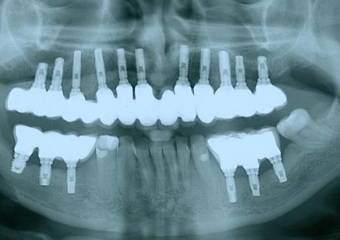

Implantes instalados com cicatrizadores

Raio X final